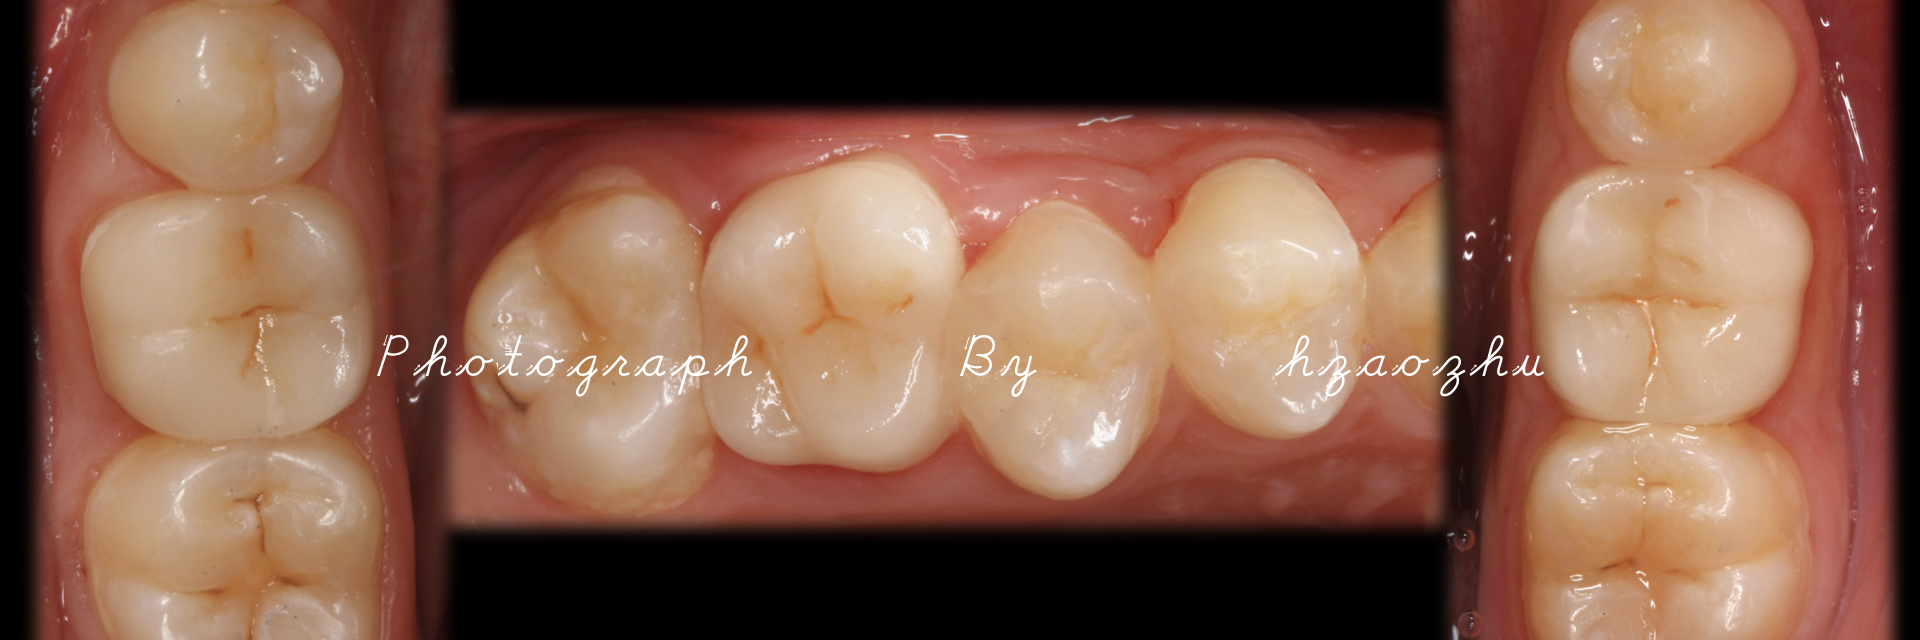

嵌体|E.Max .16.36.46

温州佳洁口腔 朱照鸿 医生 | 技师:尹群